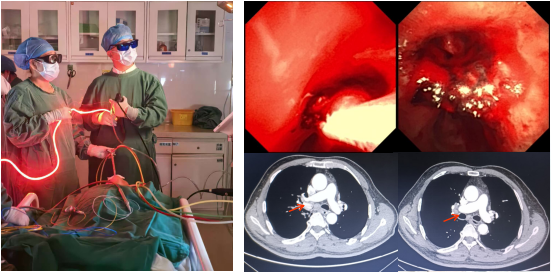

气道肿瘤光动力治疗